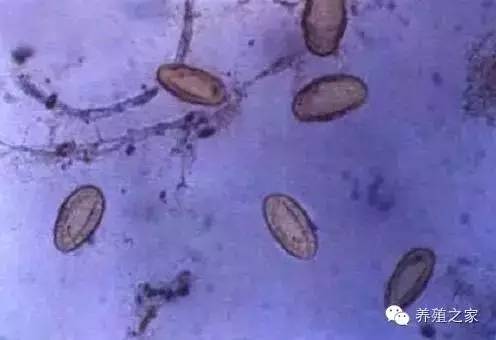

【羊肝片吸虫病】肝片吸虫虫卵的形态